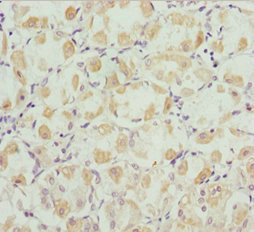

• Immunohistochemistry of paraffin-embedded human gastric cancer using CSB-PA846671ESR1HU at dilution of 1:100

IHC 1:20-1:200